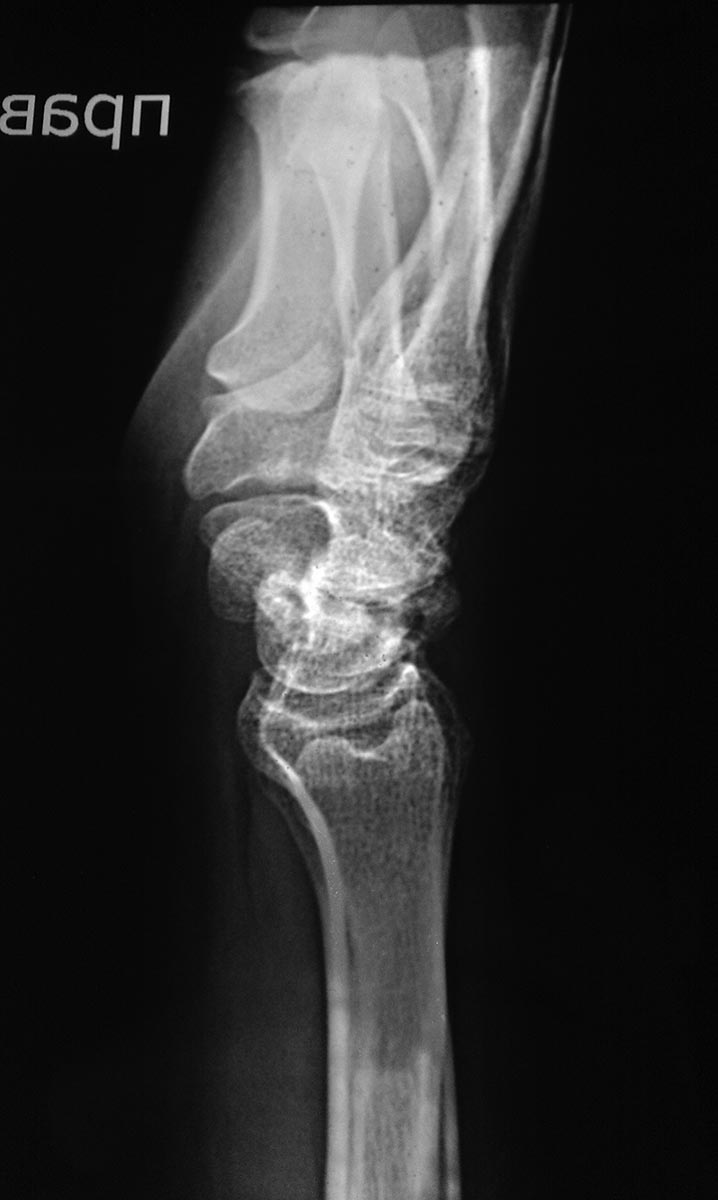

Свежего перелома не вижу. Есть несросшийся перелом ладьевидной кости. Также артроз л/зап. сустава уже есть, видимо травма старинная.

перелом явно старый, более 1 года. Сформировался ложный сустав, есть признаки артроза. Учитывая молодой возраст, возможно стоит рассмотреть остеосинтез винтами Герберта с костной аутопластикой. Надо зачистить шип на ладье, возможно удалить верхушку шиловидного отростка лучевой кости. Еще- в плане личного восприятия- снимки и репозиция все-таки делаются В АППАРАТЕ, а не НА.

Ложный сустав ладьевидной кости не вызывает сомнений, причём до 4.02.2016 - без клинической манифестации. 4.02.2016-травма и подвывих на уровне ложного сустава.

Ну о каком свежем переломе может идти речь??? Этому перелому уже 3-4-5 лет!!!! Сделайте компьютерную томографию и Вы поймете однозначно, что как проксимальный так и дистальный фрагменты нежизнеспособны и полны кист и никакая костная пластика их не спасет!!! Так же имеется грубые изменения в самом суставе!!! Диагноз - деформирующий артроз кистевого сустава III cт. на фоне псевдоартроза ладьевидной кости с фрагментацией и асептическим некрозом фрагментов ладьевидной кости SNAC (Scaphoid Nonunion Advanced Collapse). В данном случае есть 2 пути - 1 - провести консервативную терапию - гипсовую лонгету, НПВП, физ. методы и аппараты внешней фиксации здесь абсолютно не нужен!!! и беречь эту кисть "как зеницу ока", возвращаясь к такому лечению 2-3 раза в год!!! и 2 вариант более радикальный и более действенный (он остановит дальнейшее разрушение кистевого сустава, уберет боль, но оставит движения на таком же уровне) - эксцизия ладьевидной кости, четырехсуставной артродез с фиксацией специализированной пластиной Spider или же менее затратный вариант - винтами TwinFix или же винтами Герберта, частичная резекция шиловидного отростка лучевой кости кистевого сустава.

При таком сильном растяжение сустава, ждать консолидации, как в ГКБ №4 г. Москвы, я бы не стал, не срастётся. Изначально мы имеем ложный сустав ладьевидной кости и SNAC 1-й стадии. Вариант с 4-х угольным артродезом рановат, т.к. нет признаков асептического некроза проксимальной части ладьевидной кости поэтому есть шанс добиться консолидации.